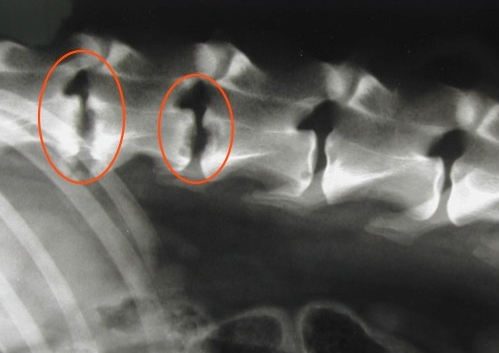

디스크의 감염성 질환인 diskospondylitis가 PSS에 의해 유발될 수 있다는 내용의 논문이다.

혈관의 비정상적 구조로 이하여 면역 작용의 약화가 있을 수 있고 이로 인한 패혈증(?) 때문이라고 말할 수 있다.

다만 diskospondylitis가 있다고 하여 PSS는 아니라는 점을 명심해야 한다.